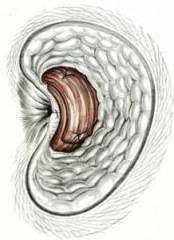

Zur Feindiagnostik des Schliessmuskels erfolgen eine Analspinctersonographie und Manometrie. Diese speziellen Untersuchungen werden durch Dr. Franz Eigenmann, Chefarzt Gastroenterologie, durchgeführt.

Bei der Analsphinctersonographie (Abb. oben) wird der anale Schliessmuskel mittels Ultraschall beurteilt. Die Untersuchung liefert entsprechende Hinweise auf Muskeldefekte (siehe Pfeile), welche beispielsweise nach schweren Geburten auftreten können.